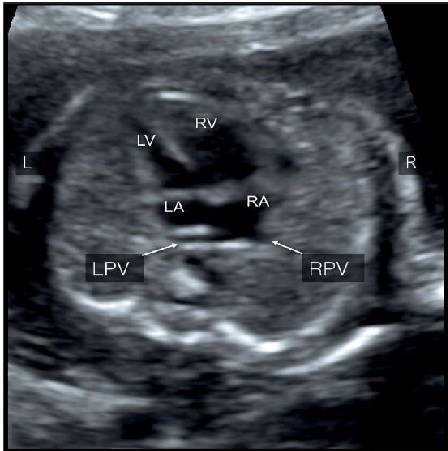

Hình 2: Mặt cắt ngang 4 buồng tim: Hình ảnh bất thường hồi lưu tĩnh mạch phổi toàn phần (TAPVR) thể trên tim (type I: supracardiac). Hình phóng to phía sau tâm nhĩ trái B và C. Lưu ý tâm thất phải (RV) và nhĩ phải (RA) lớn hơn tâm nhĩ trái (LV) và thất trái (LA) do tĩnh mạch phổi gián tiếp đổ vào nhĩ phải. Cả hai tĩnh mạch phổi phải (RPV) và tĩnh mạch phổi trái (LPV) đều không đổ vào nhĩ trái mà đổ vào tĩnh mạch hội lưu (confluent vein) “mũi tên rỗng”.